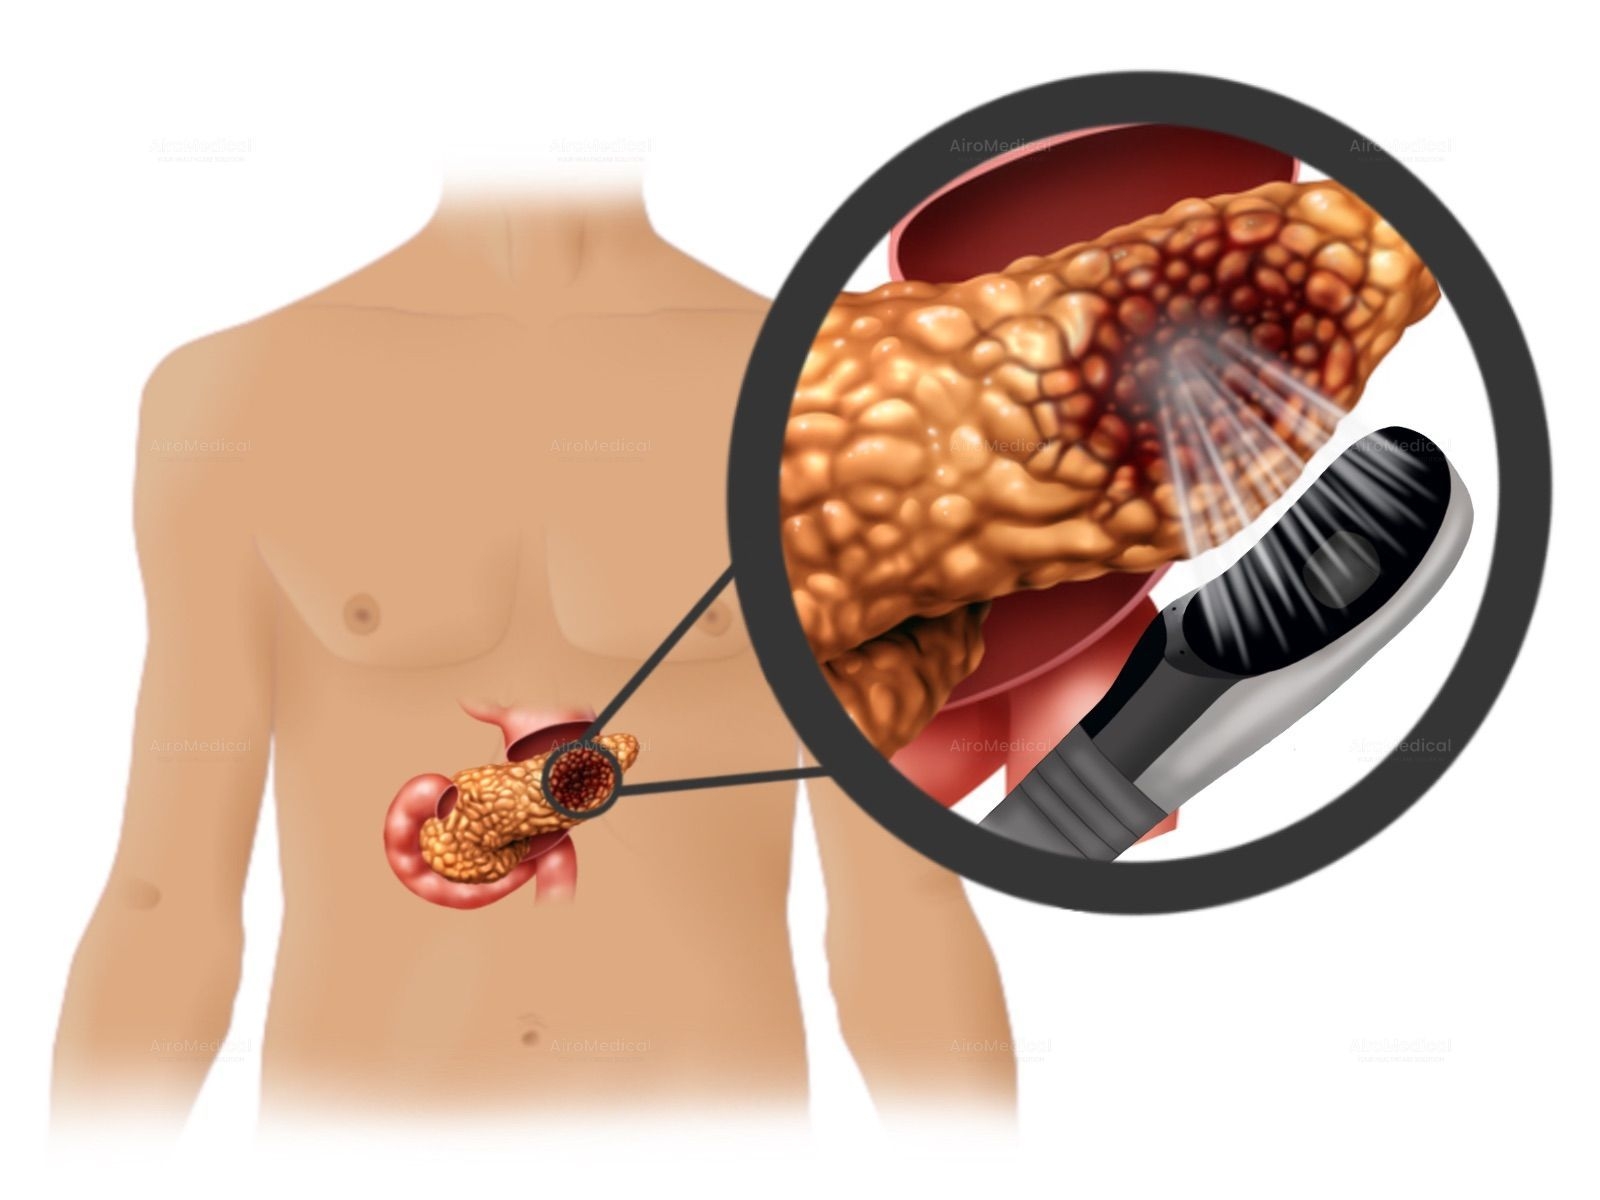

Is University Hospital Frankfurt suitable for patients with cancer?

It is one of the largest institutions dealing with cancer treatment. The oncology unit has a spiral tomograph, a gamma knife, PET, and other latest-generation equipment. Moreover, the team has performed hundreds of successful operations to treat the most complex oncological diseases.